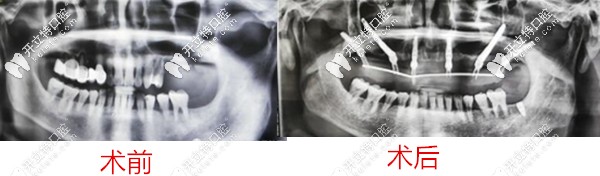

2、弟弟,60歲

種牙前牙齒問題:全口牙松動(dòng)、多顆缺失,牙槽骨流失;

種植方案:雙側(cè)穿顴穿翼,種植6顆恢復(fù)14顆。